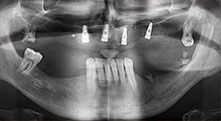

Pourriez-vous décrire brièvement par exemple comment vous procédez pour mobiliser les blocs osseux en vue d’une greffe ?

Pr Bratu : Nous préférons prélever l'os sur la crête oblique externe de la mandibule postérieure, et non dans la région interforaminale. Après l'incision des tissus mous, nous utilisons les nouvelles scies pour définir la quantité d'os à prélever. De la même manière, nous les utilisons également pour la totalité de la préparation dans presque 80 % des cas. Nous avons également parfois recours à d'autres instruments piézoélectriques et, pour terminer, à un burin pour mobiliser le bloc. Nous trouvons cette technique chirurgicale très efficace.

Pr Bratu : Nous avons volontiers recours à la technique sandwich pour les augmentations mandibulaires latérales. La préparation d'un couvercle osseux est réalisée à l'aide de la scie piézoélectrique et le fragment crestal est fixé à l'aide de microvis. Nous plaçons un mélange de matériau de substitution osseuse autologue et xénogénique entre les deux. Cela fonctionne très bien. Il faut toujours s'assurer que les coupes verticales aient des dimensions suffisantes lors du clivage de la crête alvéolaire dans la mandibule. Sinon, l'os risque de se casser facilement.